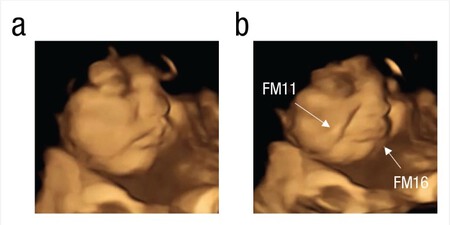

En cambio, cuando los bebés son expuestos al sabor de la col rizada o kale, la mayoría hace un gesto de desagrado. Estira las comisuras de los labios hacia abajo, haciendo un gesto de presión, lo que solemos asociar con cara de disgusto, tristeza o llanto.

Col-rizada-bebe Bebé antes y después de ser expuesto al sabor de la col rizada